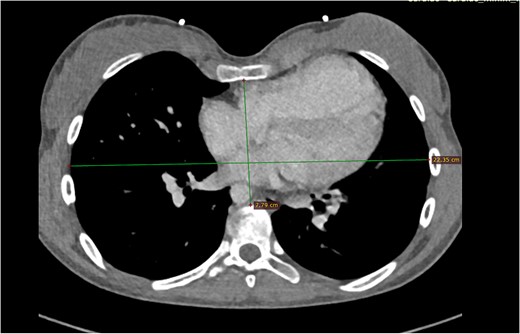

The first case involves a 17-year-old female with a medical history during infancy of a modified Blalock–Taussig Shunt in 2005 and TOF repair in 2007. Now the patient presents with severe pulmonary valve regurgitation and known pectus excavatum. The diagnosis was confirmed via echocardiography, computed tomography, and magnetic resonance imaging (MRI) scan, with a calculated regurgitant fraction of 47%, a right ventricular ejection fraction (RVEF) of 42%, and severe pectus excavatum, with a Haller index of 5.1 resulting in compression of the basal RV (Fig. 1).